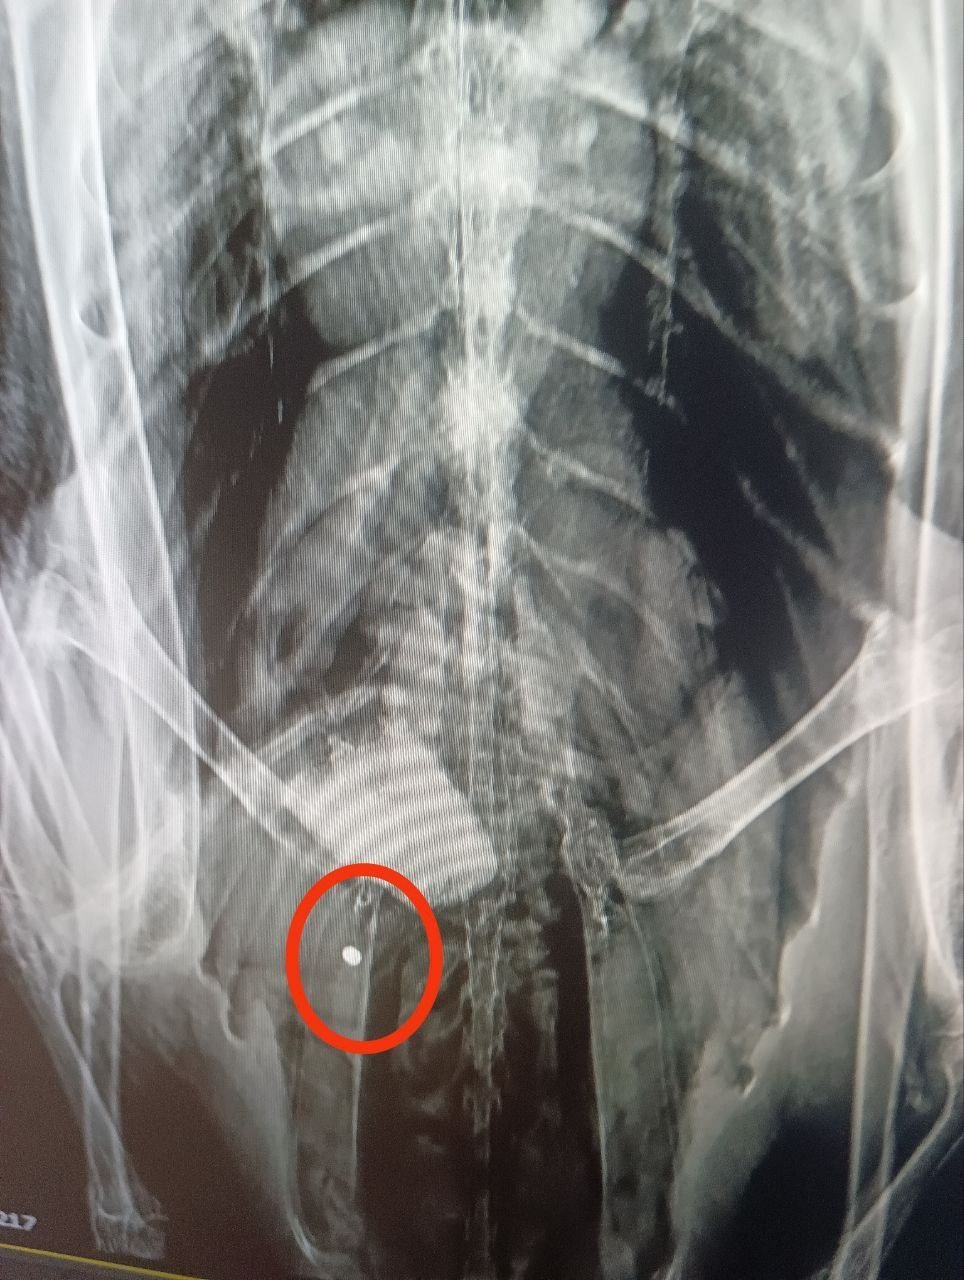

Після цього птахів відвезли до ветклініки на рентген. Волосінь фахівці так і не знайшли, зате знімок показав у тілі одного з лебедів дві кулі від пневматичної зброї.